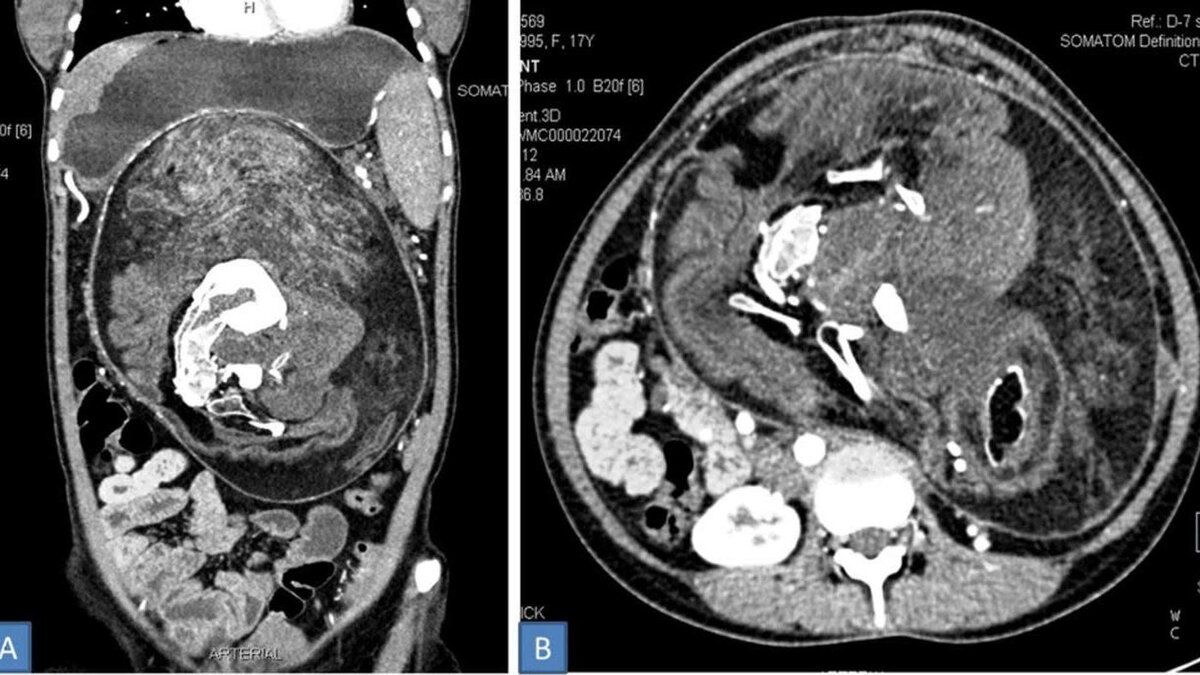

Фото Kumar, et al (BMJ Case Reports).

Компьютерная томография утробного плода в плоде.

Сначала медики заподозрили у пациентки опухоль, но углубленное исследование показало наличие отложений кальция в форме позвонков, рёбер и длинных костей. Эта аномалия известна в медицине как утробный плод в плоде. Считается, что она возникает на раннем этапе беременности близнецами. В это время оба плода имеют общую плаценту, и один из них "оборачивает" собой другого. Обычно такая ситуация заканчивается выкидышем.